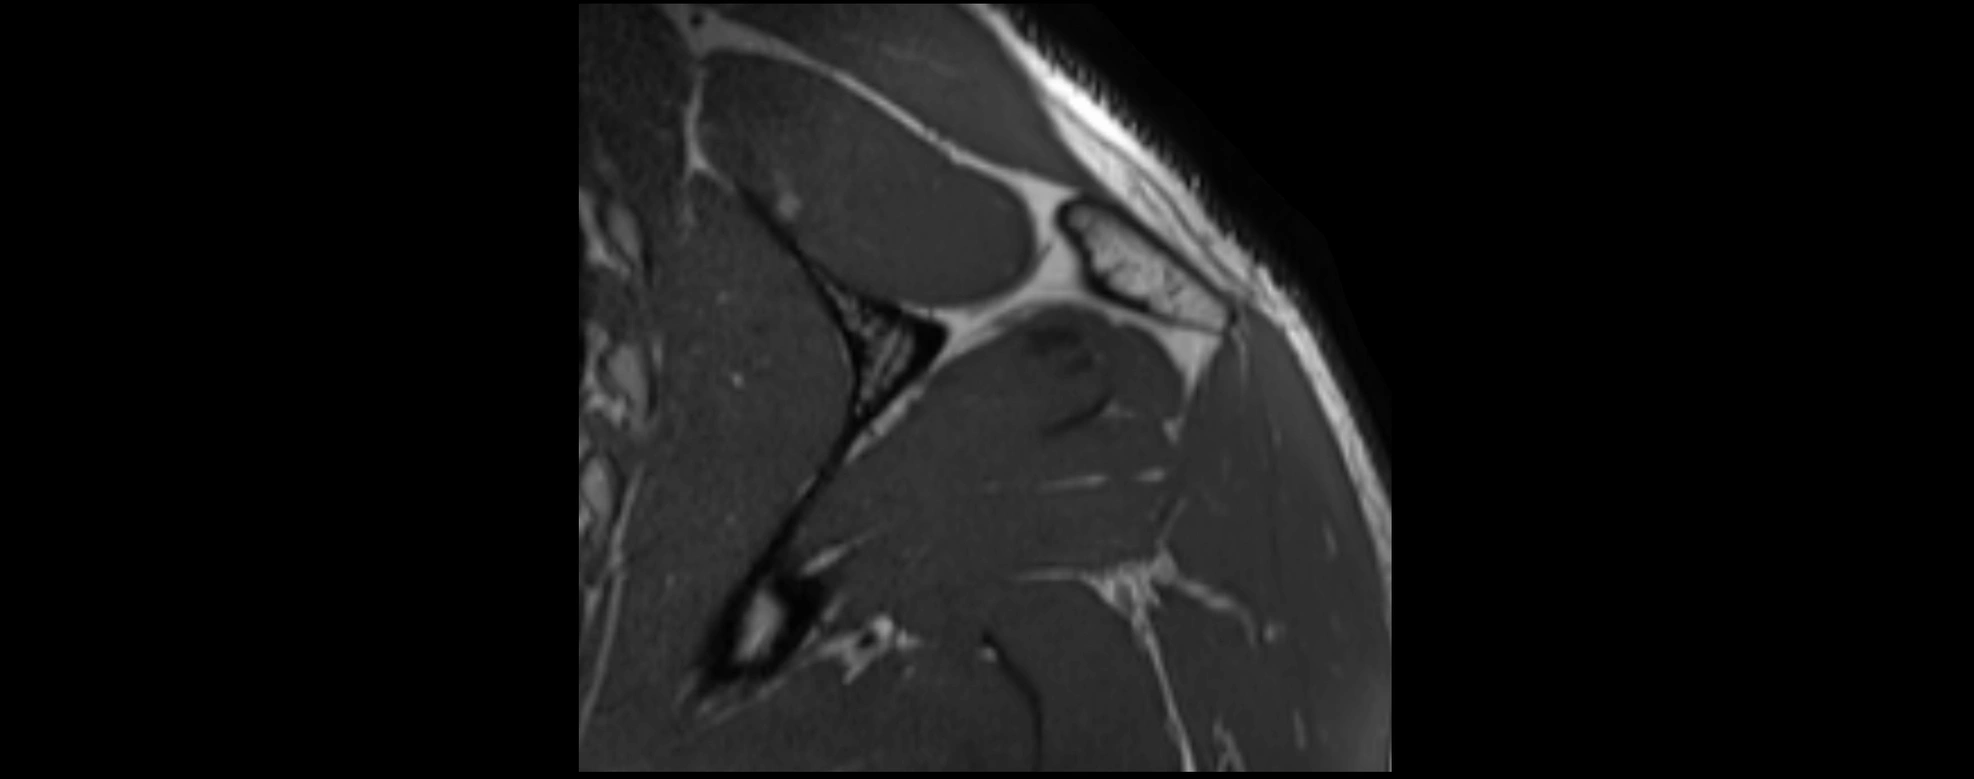

MRI images

image